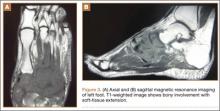

CT showed permeative destruction of left foot bones, including the calcaneus, navicular, cuboid, and cuneiform bones and all metatarsal bones except the first. Invasion through the overlying cortex of the involved bones indicated aggressive biological activity of the tumor (Figure 4). MRI showed a destructive bony lesion of the mentioned bones associated with the soft-tissue mass (Figure 3).